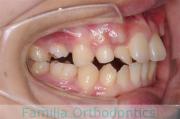

歯並びを治したいということで来院されました。下あごがやや右側に偏位して後退している、上顎前突(出っ歯)でした。上下左右から小臼歯を抜歯して、歯科矯正用アンカースクリューを併用したマルチブラケット法にて治療を行いました。約2年、24回の来院をしていただきました。

下顎の後退はいびきなどの上部気道の障害が出やすいと考えられます。

右側

正面

左側